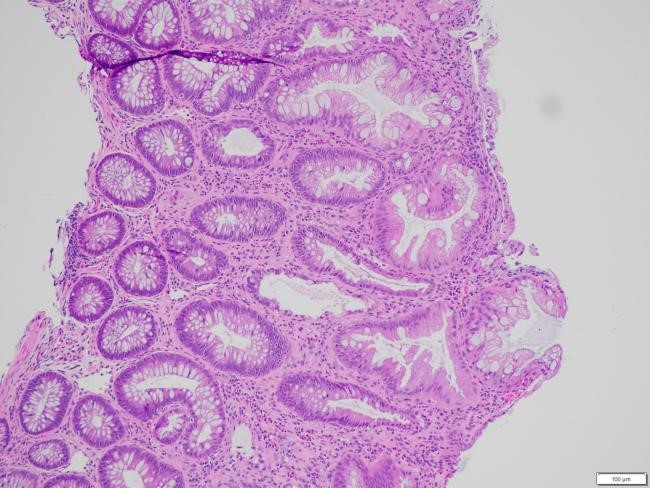

Kết quả mô bệnh học

Trên 04 tiêu bản làm từ bệnh phẩm nhận được, nhuộm HE và PAS thấy:

Ống 1 (đại tràng): Có 03 mảnh sinh thiết niêm mạc đại tràng nhỏ, bề mặt phẳng, tuyến chế nhầy bình thường về số lượng và hình thái. Mô đệm giữa các tuyến phù nề nhẹ, thâm nhiễm rải rác tế bào viêm mạn tính số lượng ít. Không phát hiện dị sản, loạn sản, ung thư, polyp, hình ảnh lao, nấm hay bệnh Crohn.

Ống 2 (đại trực tràng): Niêm mạc dày nhẹ, tuyến chế nhầy có vùng kéo dài nhẹ nhưng vẫn lành tính. Biểu mô phủ có vùng thoái hóa, bong trợt. Mô đệm xen giữa các tuyến thâm nhiễm nhiều tế bào viêm mạn tính và bạch cầu đa nhân trung tính, rải rác có nang lympho. Không thấy dị sản, loạn sản, ung thư, polyp hay viêm đặc hiệu.

Hình 3: Hình ảnh giải phẫu bệnh nhuộm Hematoxylin-eosin x 100